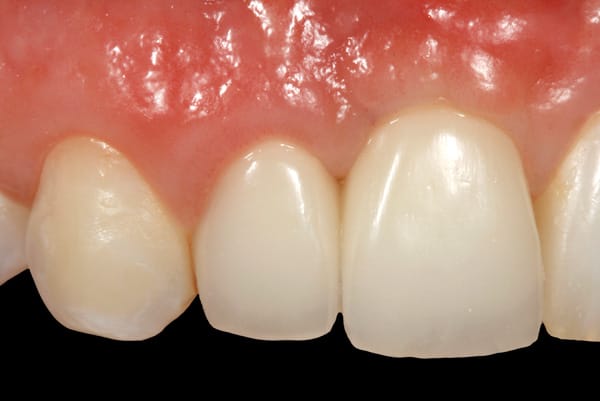

After 6 months of healing of the implant, stage 2 uncovering was performed and the mucosal tissues were allowed to mature for another 2 to 3 weeks. A temporary screw-retained implant cylinder (PreFormance® Temporary Cylinder, Biomet 3i) was joined to the implant and acrylic (Super-T, American Consolidated Mfg, www.pattersondental.com) crown (Figure 8). The subgingival shape of the temporary was modified with additional acrylic and the technique of non-surgical tissue sculpting, which was developed to provide the proper emergence profile to the mucosal tissues.27 It is important that the temporary blanching (ischemia) of the mucosal tissues dissipate after 10 minutes (Figure 9). After 3 weeks, soft-tissue scalloping through gingivectomy was done to recreate the proper shape (ie, gingival zenith)28 and proportion for the mucosal tissues (Figure 10). Fiberotomy on the distal aspect of tooth No. 7 was not performed during treatment; therefore, this papilla was slightly more incisal (longer) than the adjacent papillae (Figure 11). A final impression was made of crown No. 7 and implant No. 8 at the implant level to enable a working cast to be made in the laboratory. An all-ceramic custom abutment was made for implant No. 8 (BellaTek® Encode, Biomet 3i), and splinted full-coverage units were made for crowns No. 7 and No. 829 (Figure 12). The custom abutment was seated intraorally and torqued according to the manufacturer’s recommendation. The crowns were luted with provisional cement (Tempbond® NE, Kerr Dental, www.kerrdental.com) and maintained at 4-month recall intervals (Figure 13). Note the health of the periodontal tissues and their integration with the adjacent teeth and surrounding gingiva, taking a complex esthetic and functional problem for a patient with a high smile line and providing a predictable restorative and esthetic outcome (Figure 14).